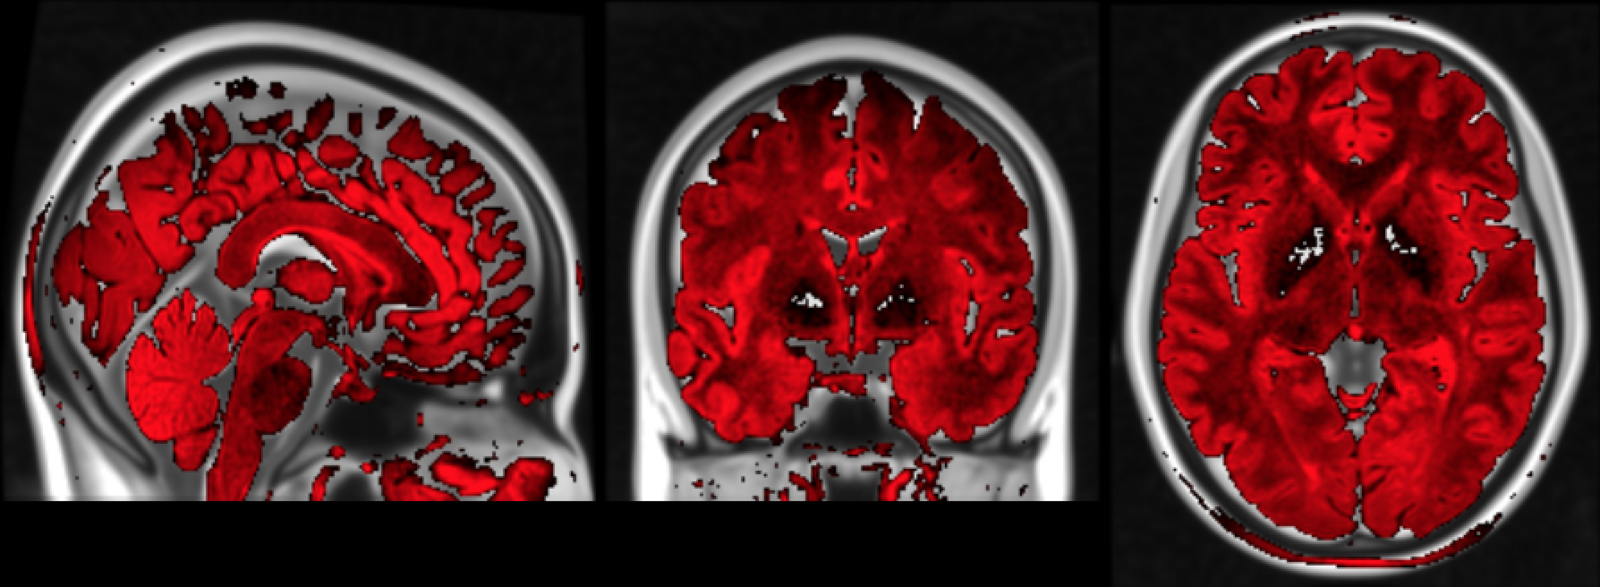

3. Cortical Lesion Filling

Lesion filling algorithms in MS try to inpaint T1 hypo-intense WM lesion (about 30% of FLAIR-appearing lesions) as Normal-Appearing White Matter (NAWM).

This procedure has shown to improve:

- Segmentation reliability

- Cortical Thickness estimation in longitudinal studies.

This procedure has NOT been studied before over Cortical Lesions: only ~15% appear as hypo-intense in T1.